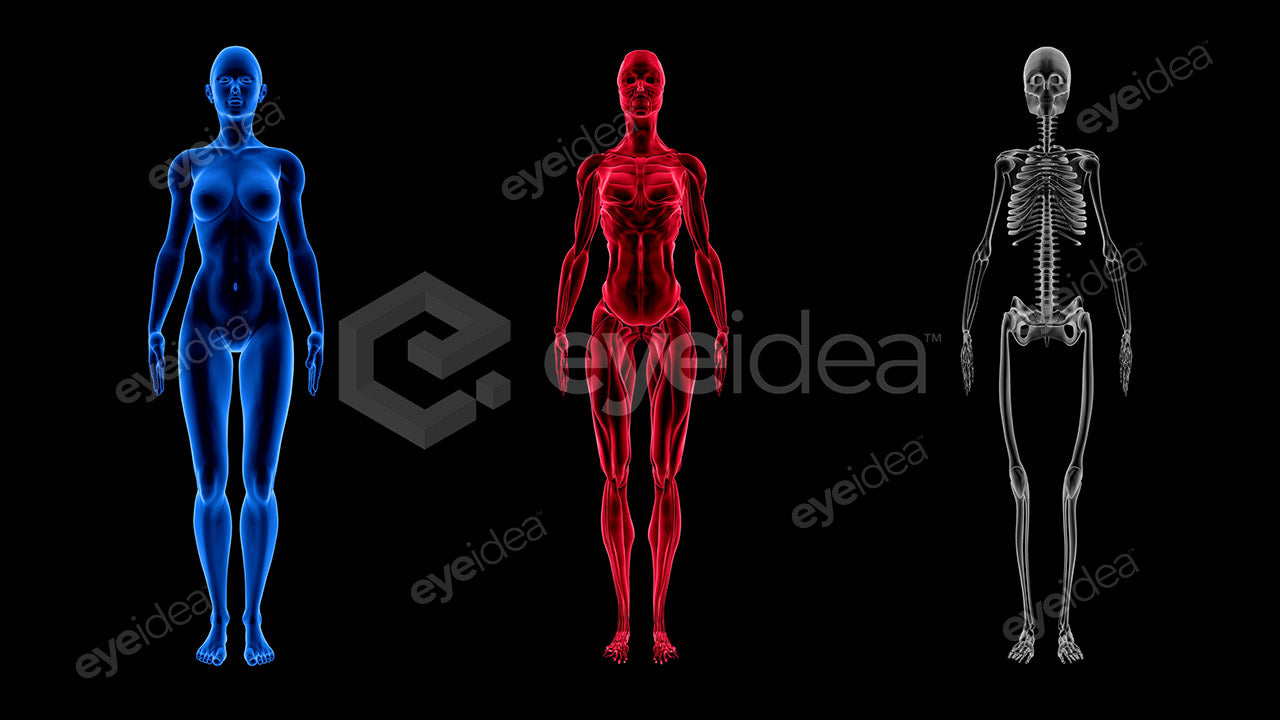

Versatility and Variety

Our Stock-Packs™ are curated to include a varied

range of angles, motion, styles and formats,

ensuring that creators can find the assets

they want fast and easy.